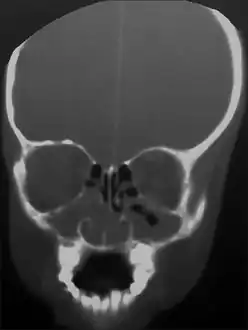

CT PNS showing the bilateral maxillary and nasal polyps

CT PNS showing the perforation of right side of hard palate